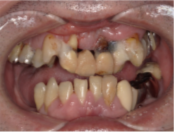

オールオン4の症例紹介①

Before

After

主訴

歯がぐらぐらして噛めない

治療内容

全ての歯を抜歯し、

上顎、下顎に対するインプラント治療を行った。

治療費

4,092,000円(税込)

治療期間

1日

通院回数

3回

※治療回数は1回

想定されたリスク

※最終的な歯が入るまでは仮歯となりました。

オールオン4は、4本のインプラントで片顎の人口歯を支える治療法です。重度の歯周病や総入れ歯の方に適しています。